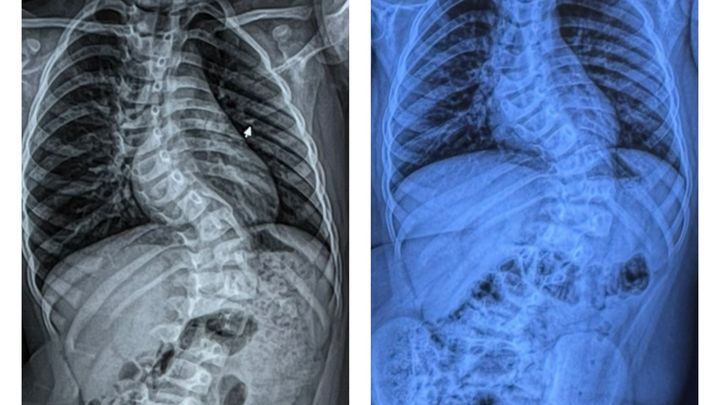

Koledyn was diagnosed with adolescent idiopathic scoliosis, double curvature, known as the (“S”) curved spine in November of 2022.

Scoliosis is a spinal deformity that causes an abnormal side-to-side curve in the spine..

Since, Koledyn has been seen at Essentia Health in Duluth, by Dr.Kathryn Huff and several other pediatric othoropedic specialists. Koledyns spine at this time had a 67 degree curve and a 43 degree curve.

Dr. Huff decided it was best for Koledyn to start his scoliosis journey with bracing. Over the last 3 years Koledyn has had two different Boston thoracic body braces, that are meticulously designed, specifically to his body and curvature.

It works by applying pressure to the spine, with hopes of maintaining and or correcting the curve, unfortunately it hasn’t helped enough, resulting in Koledyn needing spinal surgery to avoid risk of deformity, pain and damage to his organs.